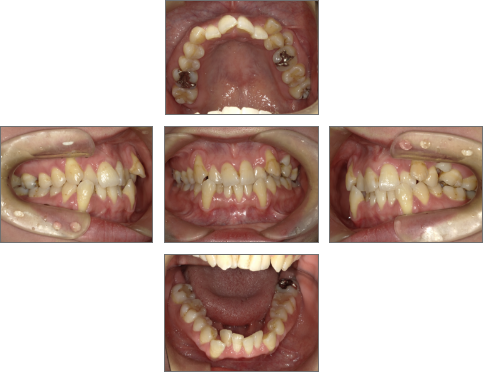

【治療前】

●主訴

歯並びのガタガタが気になる。歯磨きがしづらく、将来、歯が悪くなってしまうのではないか、心配。

●診断名あるいは主な症状

叢生

●年齢

31歳2ヶ月

●治療に用いた主な装置

セラミックブラケット

●抜歯部位

右上4番、左上6番、右下4番、左下4番・8番(親知らず) 計5本抜歯

●治療期間

約2年

●メンテナンス頻度

月1回

●治療費用(税抜)

約1,100,000円